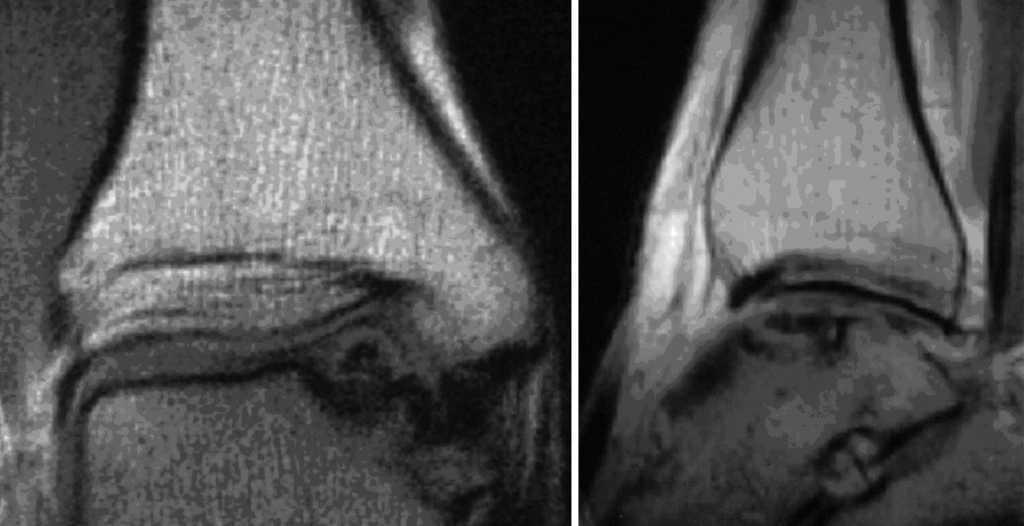

A los seis meses de la cirugía la RMN ya mostraba una buena integración del bloque óseo y del cilindro implantado. Concretamente a nivel de la tibia, no se encontraron edema perifocal, vetas de esclerosis, ni incongruencia de las superficies articulares (fig. 15).

Figura 15

Las radiografías no mostraban ninguna evidencia de artrosis ni escalones a nivel del bloque óseo incorporado (fig. 16).

Figura 16